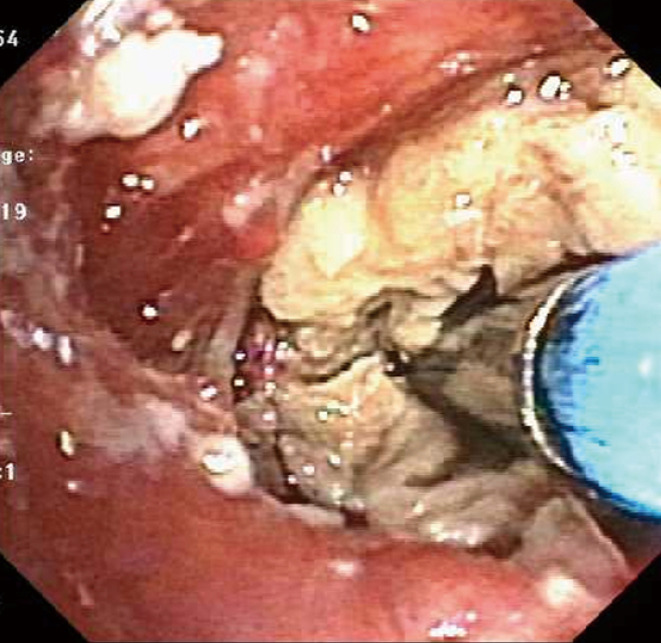

Figure 3.

Examples of iatrogenic foreign body aspiration. (A) A 78-year-old gentleman was emergently intubated for acute respiratory failure and a tooth was dislodged into the bronchus intermedius. Bronchoscopy was performed for hemoptysis a few days after the intubation and the diagnosis of iatrogenic foreign body impaction was made. (B) Image of a broken disposable bronchoscope (AMBU®) that was inadvertently introduced via “Murphy eye” of a size 8.0 endotracheal tube. This resulted in iatrogenic foreign body that required removal using a forceps. One jaw of the forceps was engaged in the lumen of the broken scope and grasped to extract in its entirety.